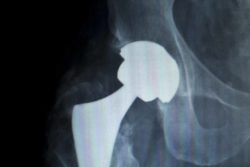

The moving parts in metal-on-metal hip replacement devices like the ASR DePuy system may grind against each other, releasing toxic metal ions into patients’ bloodstreams. This grating movement may also cause the metal parts to deteriorate and create metal shavings.

Side effects from this deterioration may include tissue necrosis, local swelling and inflammation, allergic reactions, pain, and disability. Hip dislocation and bone fractures are also common side effects. In some cases, non-cancerous tumors may develop around the implant, leading to discomfort. These side effects may indicate impending failure of the device. Device failure may require patients to undergo revision or replacement surgeries to repair the damage done by the malfunctioning device.

DePuy has settled more than 10,000 claims and lawsuits from patients who required revision surgeries after they received hip implants created by the company. Lawsuits regarding DePuy hips have been filed in the U.S., as well as in many other countries across the globe, including the United Kingdom, Canada, Australia, Ireland, Germany, and Italy. Due to these and other claims, DePuy recalled the DePuy ASR hip replacement system in 2010.